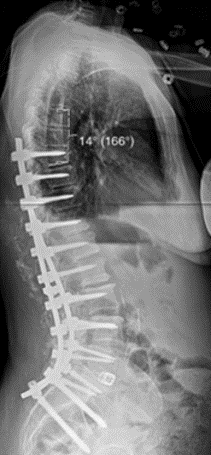

T10骨盆固定,出现交界性后凸

行翻修手术:T9/10SP截骨,延长到T4固定,预防性双侧肋骨固定(VEPTR)

图32-33 肋骨固定